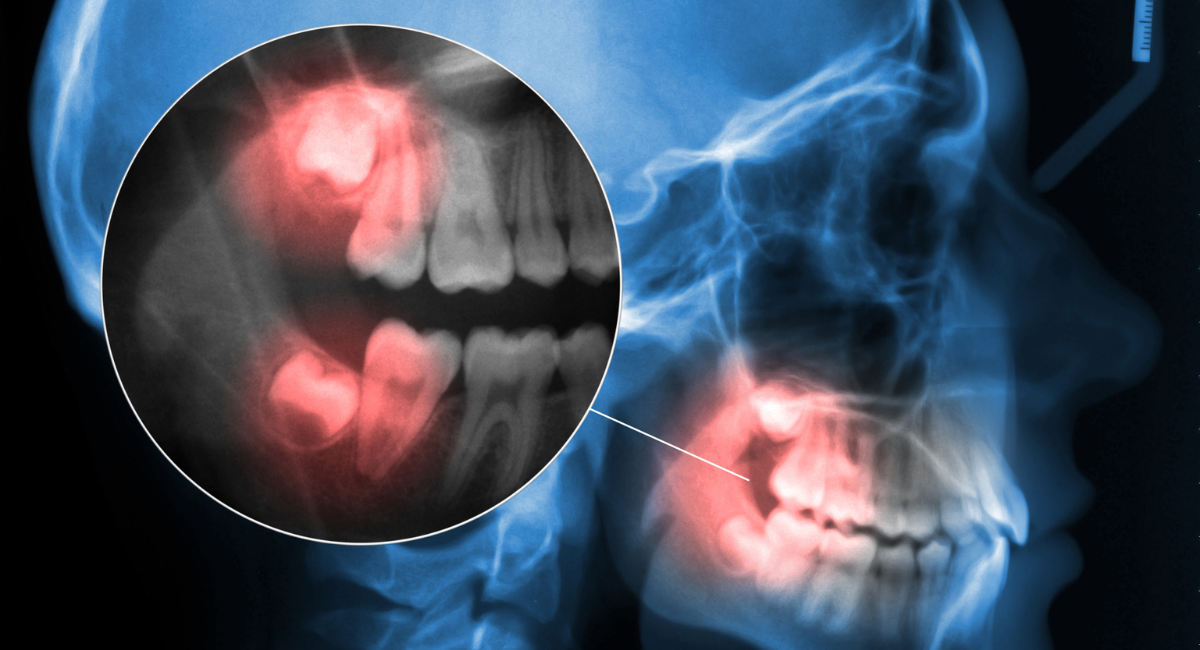

親知らずの抜歯において最も大切なのは、処置そのものよりも事前の診断です。見た目だけで「抜いたほうがよい」「今は様子を見ましょう」と判断するのではなく、歯の根の形や向き、周囲の骨や神経との位置関係まで把握することで、適切な治療方針を立てることができます。

特に下顎の親知らずは、下歯槽神経という重要な神経の近くに位置していることがあり、診断を誤ると術後のしびれなどのリスクにつながる可能性があります。そのため、レントゲンや必要に応じた精密検査を行い、リスクを想定した上で治療計画を立てることが不可欠です。

レントゲン・CTを用いた正確な診断

親知らずは、見た目だけでは判断できない要素が多い歯です。歯ぐきの中や骨の中に埋まっている場合も多く、歯の向きや根の形、周囲組織との関係性は、外からは分かりません。そのため横浜市鶴ヶ峰駅の歯医者・歯科、横浜グランアズーリデンタルクリニック鶴ヶ峰では、通常のレントゲン検査に加え、必要に応じてCT撮影を行い、立体的な情報をもとに診断を行います。

CT検査によって、

- 親知らずがどの方向に生えているのか

- 歯の根がどの程度まで形成されているのか

- 顎の骨の厚みや形状

- 重要な神経や血管との距離

といった情報を詳細に把握することができます。これにより、抜歯の難易度や想定されるリスクを事前に整理し、無理のない治療計画を立てることが可能になります。

親知らずの位置や神経との関係を見極めた治療判断

特に下顎の親知らずは、下歯槽神経と呼ばれる感覚を司る神経の近くに位置していることがあります。この神経との距離や位置関係を正確に把握せずに抜歯を行うと、術後のしびれなどにつながる可能性があるため、慎重な判断が不可欠です。